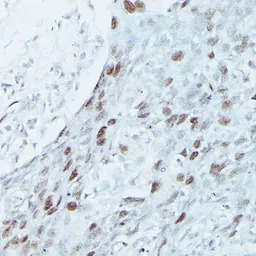

IHC-P analysis of rat brain tissue using GTX33312 MEF2C antibody.

Dilution : 1:100